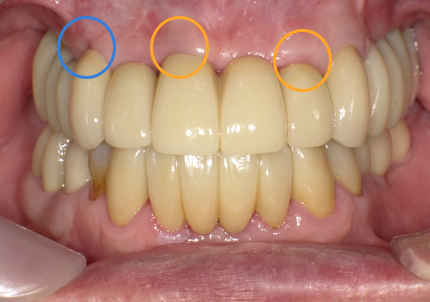

22.最終補綴物完成・装着口腔内写真(2021年1月)

23.自然な形態のインプラント歯頚部

適切な治療計画と治療技術を有することで、このような自然な形態のインプラント歯頚部を形成することができます。

【受傷後最終補綴物装着】

前歯の受傷前の歯肉の膨らみが、抜歯後にも変わらない状態を維持してインプラント治療されています。患者様、術者も結果がとても良いと満足しています。